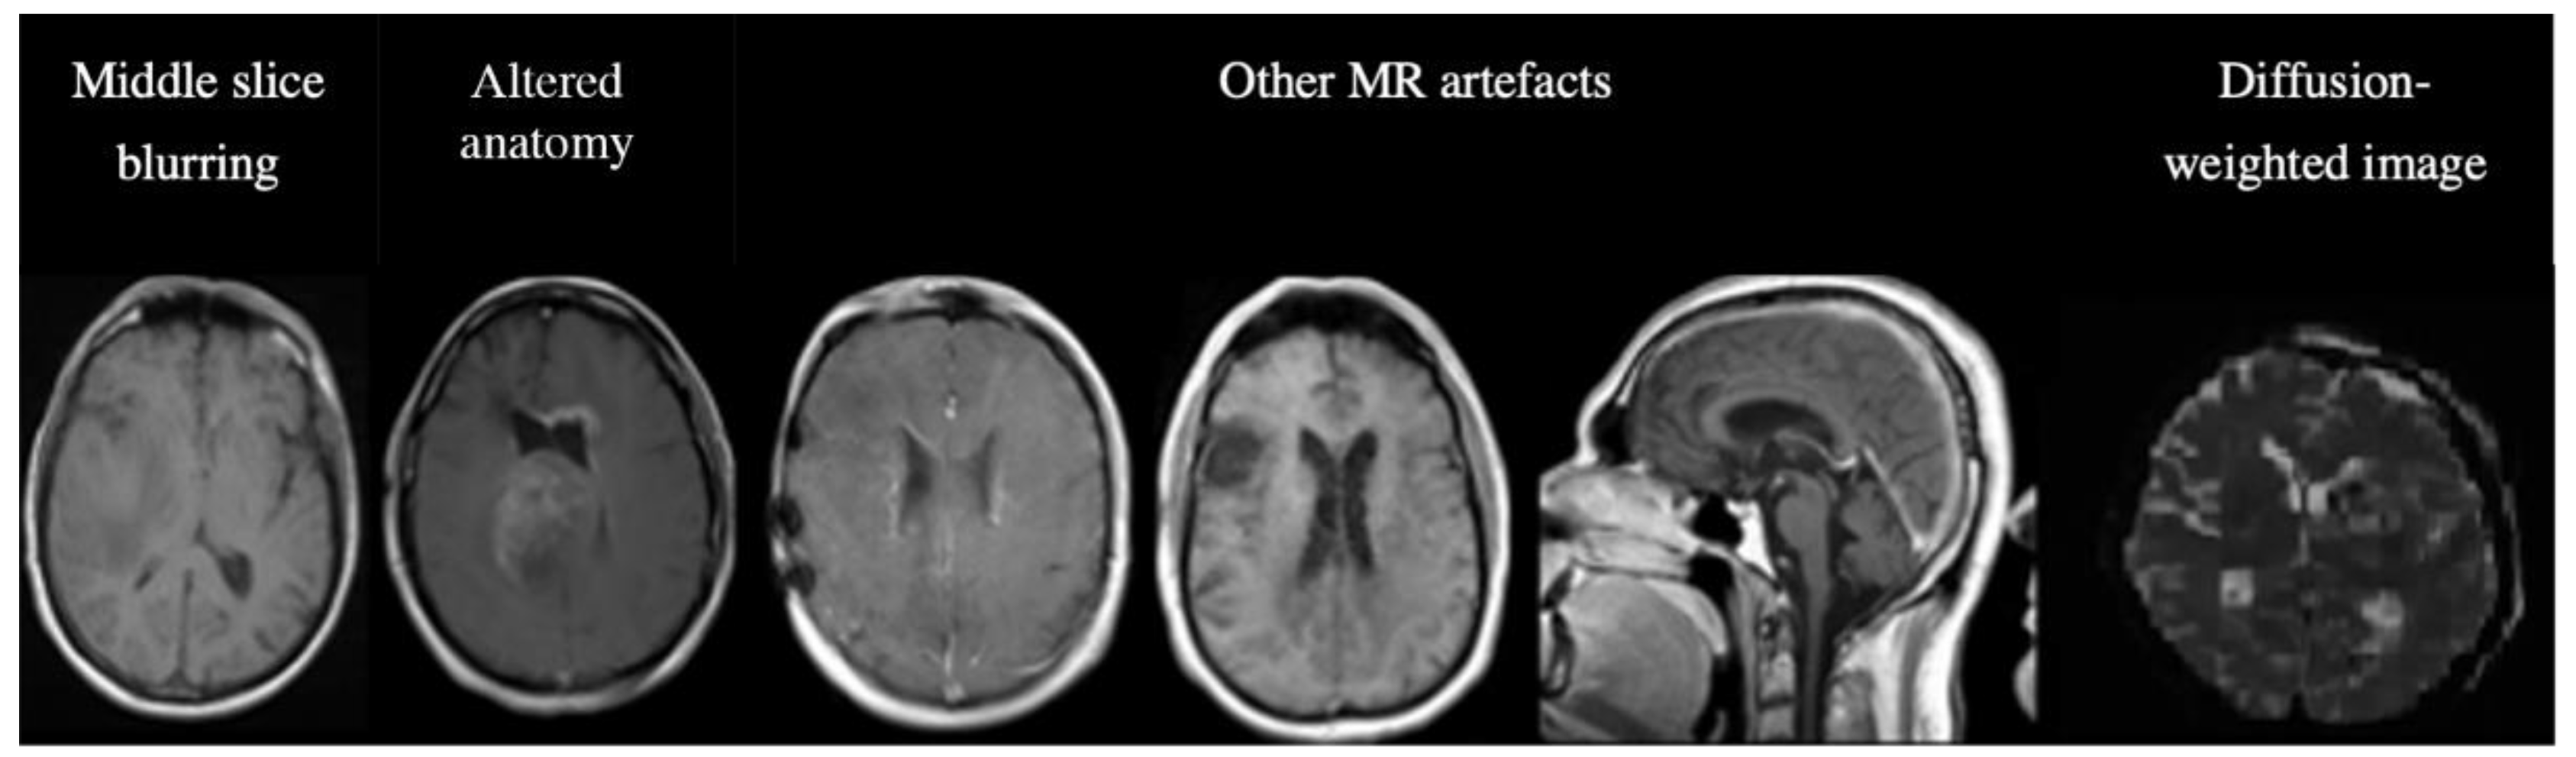

3.4. Analyses of misclassified images.

Out of the 14855 inferred images from C2 and C3, MR-Class classified 620 images incorrectly. The misclassifications can be sorted into different categories: MR artifact-middle slice blurring, MR artifacts-other, similar image content for different MR sequences (e.g., a T1w-FLAIR sequence instead of T2w), misclassified diffusion-weighted imaging (DWI) as T2w, and DICOM corrupted scans (sample images shown in Figure 6).

Figure 6. Examples of misclassified images. The first two images are examples of a misclassified MR, possibly due to blurry images (left) and alterations in expected anatomy (displaced ventricles, large tumor, right). The next three MR images show incorrect predictions due to different MR artifacts (Shading, motion, aliasing). All of these images are falsely classified as "other". The last image is a diffusion-weighted image (DWI), specifically a Trace DWI, misclassified as T2w.

A manual evaluation revealed frequent misclassification (n=122, 19.68%) if the architecture of the ventricles was altered, e.g., displaced by large tumors. This was assessed in detail: we used 122 random, correctly labeled images as a reference group. After manual segmentation of the GTVs and brain, we calculated the Euclidean distance between the brain's center of mass (CoM) and the CoM of the tumor volume. A t-test was then performed between the reference and misclassified CoM distributions. The t-test returned a p-value of 0.04, with a median CoMs distance of 46.15 voxels for the correctly labeled images and 66.31 for the misclassified images. This result shows a statistical difference between the groups, i.e., the further the GTV is from the ventricles, the less likely the image is misclassified. The frequencies of the misclassification categories are shown in Table 4.